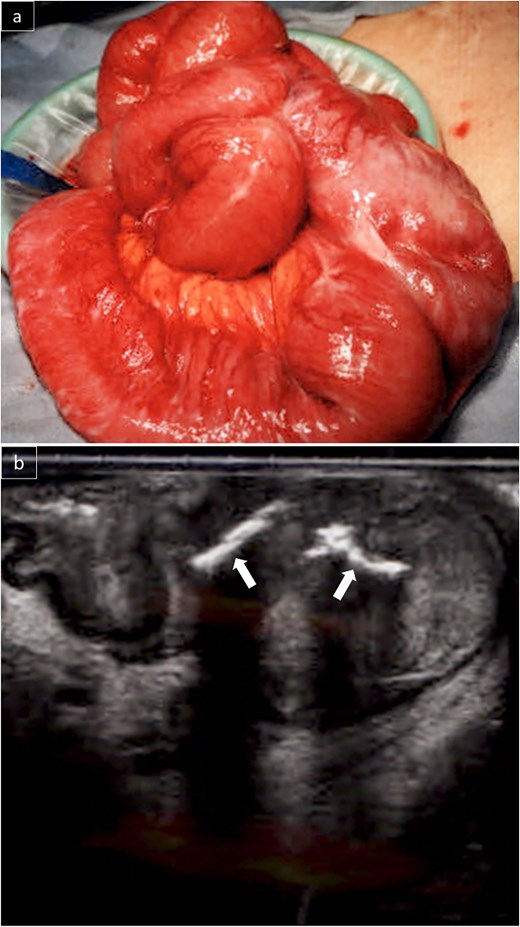

Due to persistent symptoms after 11 days of conservative management, surgery was performed. The small intestine was adherent in the right lower abdomen, with no obvious serosal abnormalities (Fig. 3a). Intraoperative ultrasonography identified a linear hyperechoic structure consistent with the foreign body on CT (Fig. 3b). A partial resection of the small intestine was performed. Grossly, a type 2 tumor containing a wire-like foreign body was identified (Fig. 4a). Pathological examination revealed that the tumor was predominantly located from the muscularis propria to the subserosa (Fig. 4b), with atypical cells present in a pseudoglandular duct-like fashion (Fig. 4c). No vascular invasion was observed in previous surgeries, and pathology from this surgery also showed no vascular invasion. Immunohistochemistry revealed that the tumor was hepatocyte-positive (Fig. 4d), CK20 negative, and CDX2 negative. The tumor was diagnosed as a small intestinal metastasis of HCC. Postoperatively, the patient showed anastomotic stenosis, but was discharged from the hospital on the 17th postoperative day. Follow-up CT showed no recurrence 4 months after surgery. The patient survived 10 months postoperatively without recurrence, with AFP significantly decreasing to 213 ng/ml 10 months after surgery.

The small intestines in the right lower abdomen were lumped together, and no lesions were exposed on the serosal surface (a). Intraoperative ultrasonography revealed a linear hyperechoic area in the mass that appeared to be a foreign body on CT (b).